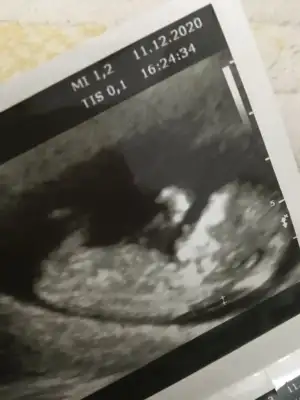

Ben de varım yaa ocak ortası tekrar gidicem o zaman artık belli olurGünaydın kızlar aranızda cinsiyeti öğrenmeyen hatta tahmin bile söylenmeyen tek ben varım galibakendimi kız için çok alıştırdım erkek derse doktor şok geçiricem sanırım